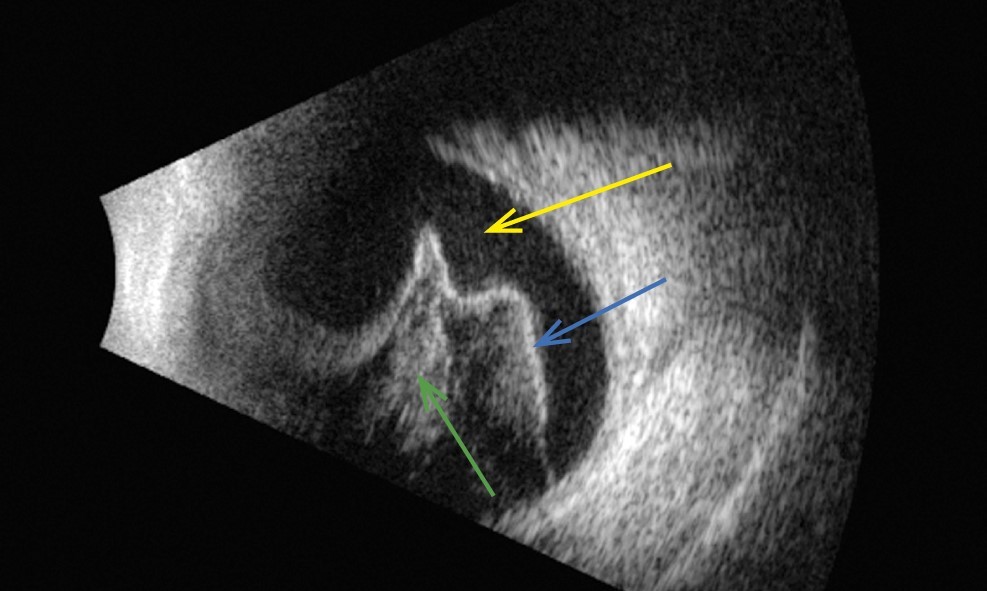

Ultrasound examination using the Quantel Medical Aviso V:5.0.0 (France) ophthalmology diagnostics scanner: the vitreous body of the right eye contains multiple inclusions visualized as bodies, flakes, chords and adhesions, with the retrovitreal areas of turbidity with various echogenicity, non-fixated posterior detachment of the vitreous body (Fig. 2).

Fig. 2. Ultrasound examination of the right eye: multiple inclusions were found, visualized as bodies, flakes (yellow arrow), strands and adhesions of various echogenicity (green arrow), non-fixated posterior detachment of the vitreous body (blue arrow).